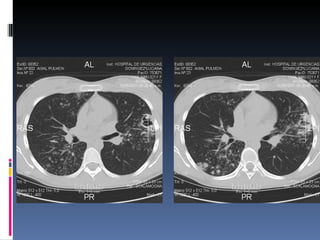

Estudios por imagen:   ECOGRAFIA ABDOMINAL Y TOCOGINECOLOGICA : sin alteraciones TAC  DE  TÓRAX c/c :

TAC de Tórax (13/06/11):

TAC de tórax: 15/06/11

TAC de Tórax(13/06/11):